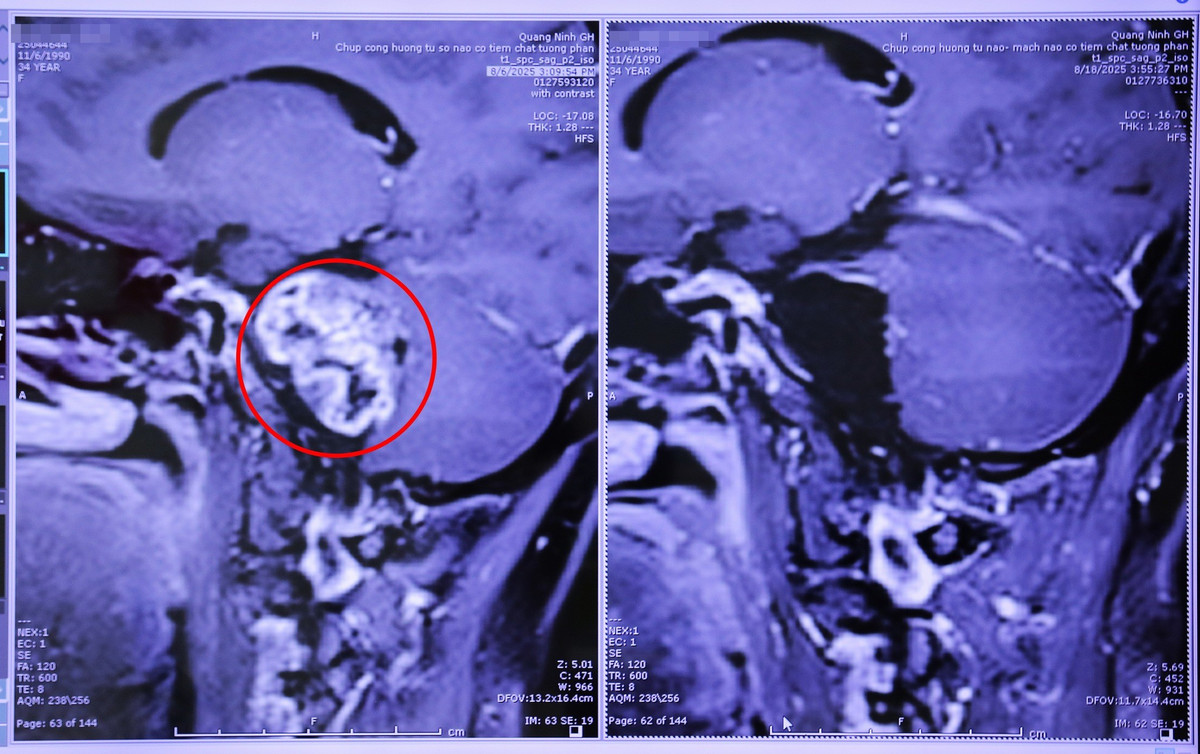

Một trường hợp khác có khối u cùng vị trí là bệnh nhân T.H.N (35 tuổi, phường Cẩm Phả, tỉnh Quảng Ninh) thường xuyên đau đầu, chóng mặt, đi lại khó khăn. Đến khám tại bệnh viện, kết quả chụp cắt lớp vi tính phát hiện 1 khối u dây thần kinh số 8 bên phải, kích thước 30x40mm, chèn ép thân não và tiểu não và các dây thần kinh sọ.

Với sự hỗ trợ của chuyên gia, kíp bác sĩ ngoại thần kinh đã thực hiện phẫu thuật lấy u thành công qua kính vi phẫu, ứng dụng hệ thống cảnh báo thần kinh trong mổ hiện đại, giúp lấy bỏ toàn bộ khối u dây thần kinh và bảo tồn cấu trúc giải phẫu các dây thần kinh.

u-nao-2.jpg

Hình ảnh chụp cộng hưởng từ khối u dây thần kinh số 8 được phẫu thuật lấy bỏ toàn bộ - Ảnh BVCC